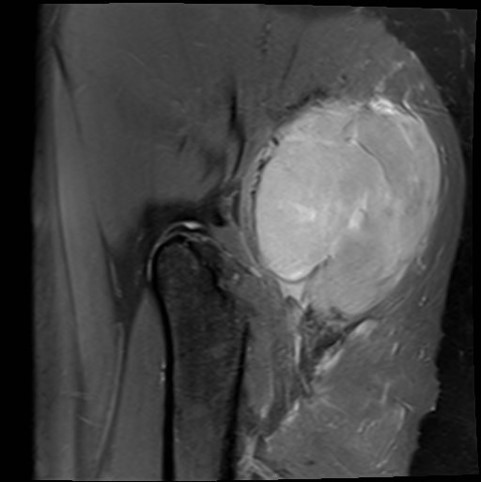

MRI

Sarcoma buttock